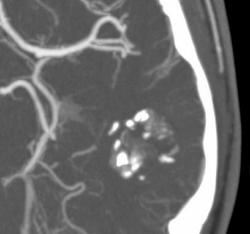

Еще одна сосудистая мальформация - кавернозная ангиома или кавернома. Раньше относили к опухолям.

Видна группа сосудистых лакун неправильной формы, кальцинаты. Перифокальных изменений нет.

Я без Вашего ведома добавил фрагменты изображения с увеличением.